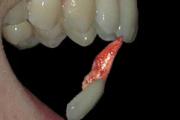

Hambatraumad

Põhimõtted – Trauma tagajärjel irdunud jäävhammast tasub alati tagasi istutada, kui õnnetuses on hammas ja alveool terveks jäänud. Kui ka hammas hiljem kaotataks, on istutamine tähtis, sest see kergendab implanteerimist ja lükkab edasi hamba asendamist proteesiga. – Mingil juhul ei Loe edasi »